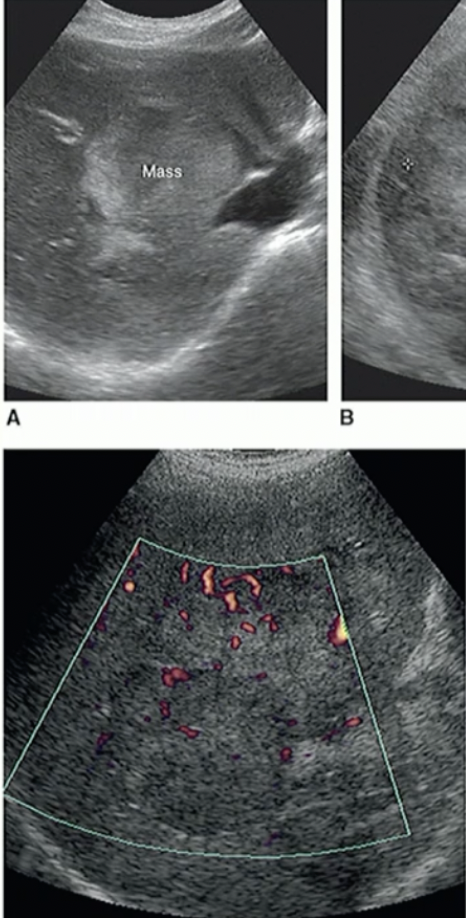

Path?

Acute Pancreatitis

Chronic Pancreatitis (Scarring on body)

Tumour on the TAIL of Pancreas